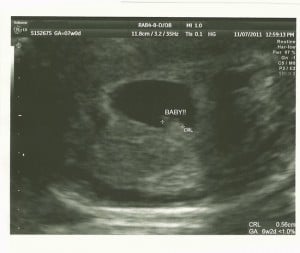

I’ve been keeping a secret from all of you. I’m not particularly good at keeping secrets, but in this case, I’ve been too afraid to make our news public, knowing what I do about how many things can go wrong. I found out about a month ago that we are expecting our 5th baby. This is good news. It is.

I had high hopes for this pregnancy. I was originally told that a cerclage and the p17 shots would give me a good shot at a normal pregnancy. Once a subchorionic hematoma (essentially an early abruption) was found on my first ultrasound the plan changed. I’m not a good candidate for a cerclage because the risk of infection is too high and l went into labor last time at least partially because the subchorionic bleed caused a uterine infection.